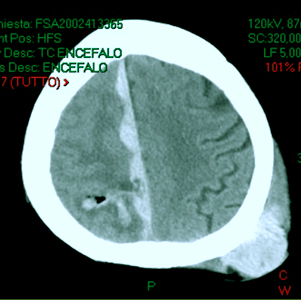

Caso 3: ematoma intraparenchimale post-traumatico